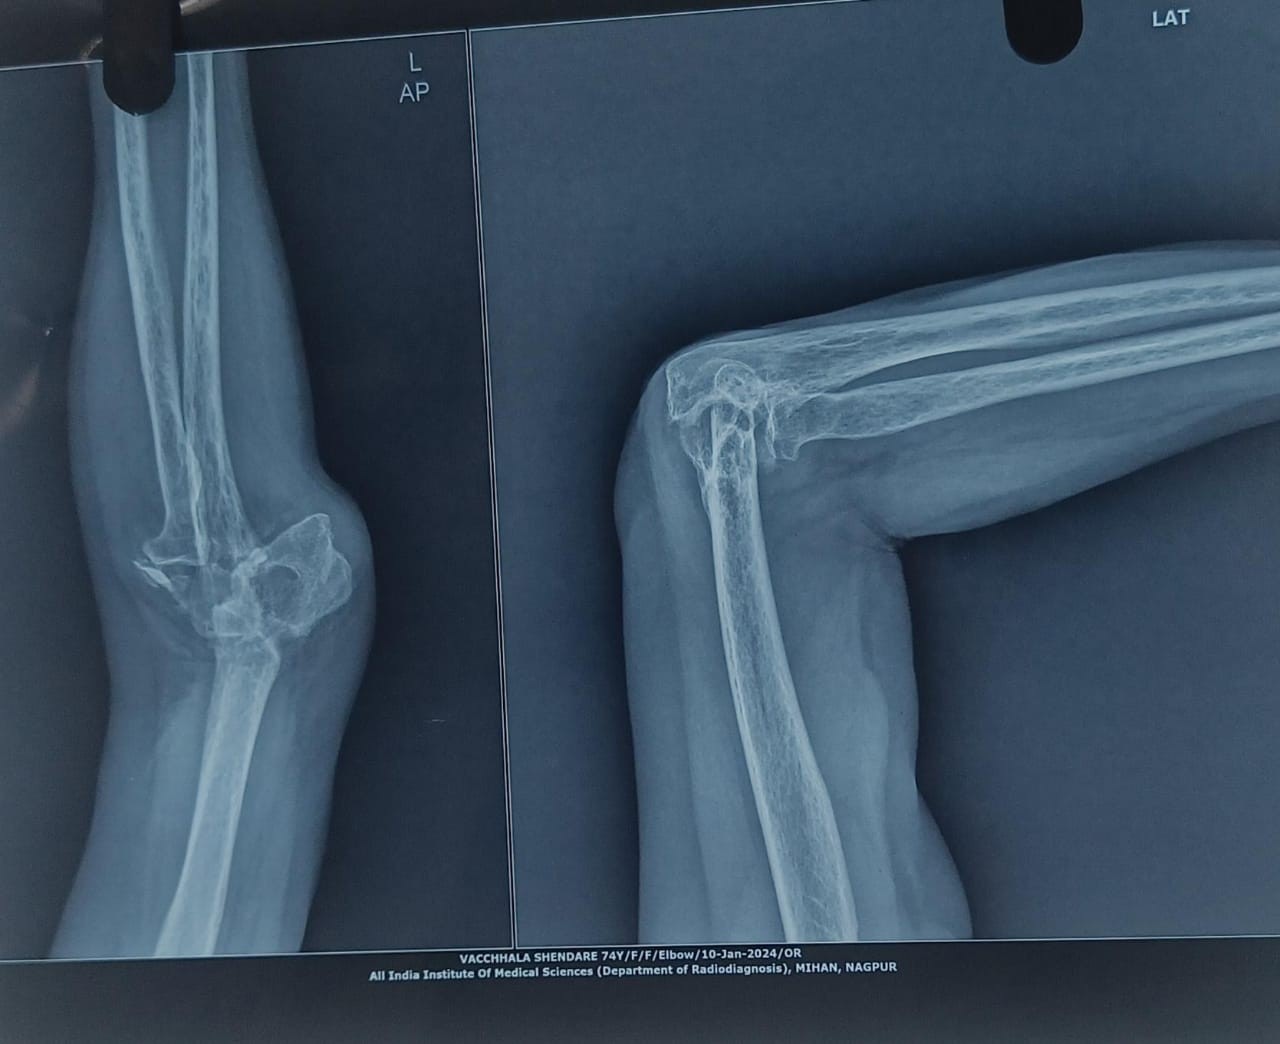

- Radiographs: Non-union of the distal humerus, joint space narrowing, articular irregularity, and subluxation (Fig. 1)

Figure 1: Pre-operative radiograph.